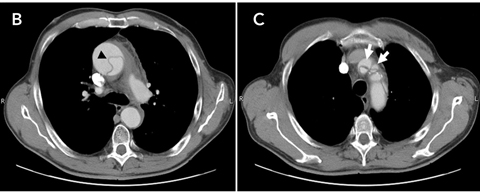

Thoracic aortic dissection generally results from a laceration of the intimal lining of the aorta. This allows blood leakage into the aortic wall resulting in a propagating separation of the aortic media, thereby creating a false blood-filled lumen.1 Hence, the major criterion for definitive diagnosis of aortic dissection includes visualisation of a so-called intimomedial flap that divides the aorta into a true and a false lumen. Several aortic imaging techniques can be used for this purpose, of which contrast-enhanced computed tomography (CT) and transoesophageal echocardiography (TOE) are the most feasible to perform in an emergency department setting.1,2 Moreover, these investigations help to localise the dissection, thereby allowing appropriate classification. Currently, the Stanford classification of aortic dissection is the most widely adopted system.1,2 This system has the virtue of merely dividing aortic dissection into two subtypes, depending on whether the ascending aorta is involved (type A) or not (type B).1,2

When readily available, contrast-enhanced CT and TOE are the preferred imaging modalities in an acute care setting. Both investigations have a comparable diagnostic accuracy and allow a definitive diagnosis of aortic dissection to be established.1,2 However, the diagnosis must first be suspected before it can be confirmed — this case serves as a reminder of this life-threatening condition’s wide variability in clinical presentation, and the need to maintain continuing vigilance.